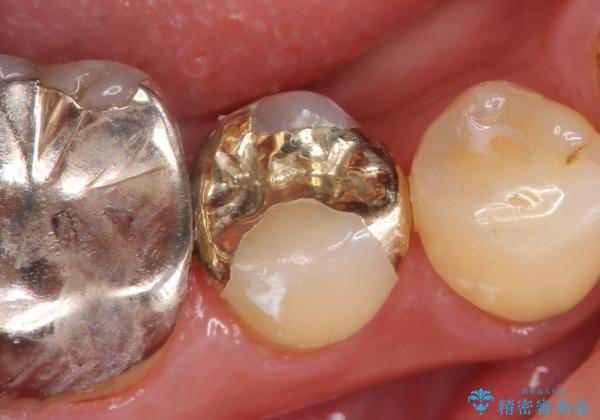

- 右下5番目の歯がしみるので診て欲しいといらっしゃった方の症例です。

古い銀歯及び虫歯を除去後、PGA(ゴールド)インレーによる修復を行いました。